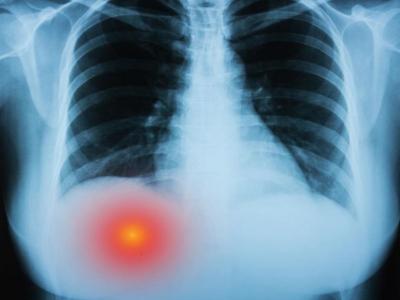

निमोनिया जैसे जीवाणु संक्रमण अक्सर पसलियों में दर्द का कारण बनते हैं। यह फ्लू जैसे वायरस या फंगस के कारण भी हो सकता है। इसके अलावा फेफड़ों का कैंसर, अन्य प्रकार के कैंसर जो आपके फेफड़ों को प्रभावित करते हैं, आपके फेफड़ों में रक्त का थक्का, एक ऑटोइम्यून बीमारी, जैसे ल्यूपस या रुमेटीइड गठिया, छाती में चोट, सिकल सेल एनीमिया और मेसोथेलियोमा आदि समस्याएं भी इसका कारण बन सकती हैं। इनके अलावा गलत मुद्रा में सोना, बैठना या खड़े होना, शरीर को देर तक स्थिर रखना, छाती की मांसपेशियों पर अत्यधिक डालने वाली एक्सरसाइज करना, बहुत भारे चीज उठाना या अनुचित तरीके से सांस लेना आदि की वजह से भी यह समस्या हो सकती है।

लक्षणों की पहचान होने पर डॉक्टर बोने स्कैन, एक्स-रे, एमआरआई या ब्लड टेस्ट की सलाह दे सकता है। इसके अलावा इसका इलाज इसके कारण और गंभीरता पर भी निर्भर करता है। कोई भी दवा या घरेलू उपाय उपयोग करने से पहले डॉक्टर से मिलना ही उचित है।